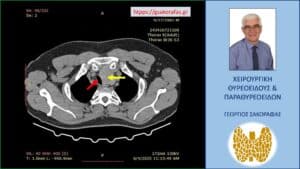

Αξονική τομογραφία – εγκάρσια διατομή. Ο διογκωμένος αριστερός λοβός (κίτρινο βέλος) που απωθεί την τραχεία (κόκκινο βέλος) προς τα δεξιά.

Αξονική τομογραφία – εγκάρσια διατομή σε χαμηλότερο επίπεδο. Ο διογκωμένος αριστερός λοβός (κίτρινο βέλος) που απωθεί την τραχεία (κόκκινο βέλος) προς τα δεξιά.